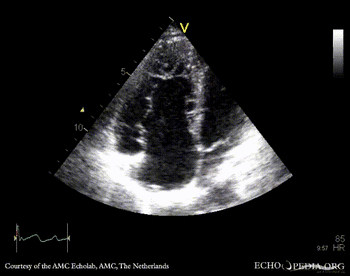

Ebstein anomaly

PLAX: enlarged right ventricle in patient with Ebstein anomaly A4CH: high insertion of tricuspid valve, enlarged right atrium and right ventricle